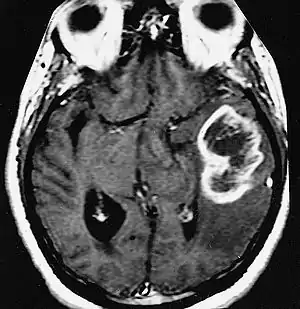

| An example of a ring-enhancement around a lesion in gliobastoma. In tumefactive multiple sclerosis, the ring-enhancement is open, not forming a complete ring. |

These atypical lesion characteristics include a large intracranial lesion of size greater than 2.0 cm with a mass effect, edema and an open ring enhancement. A mass effect is the effect of a mass on its surroundings, for example, exerting pressure on the surrounding brain matter. Edema is the build-up of fluid within the brain tissue. Usually, the ring enhancement is directed toward the cortical surface.[2] The tumefactive lesion may mimic a malignant glioma or cerebral abscess causing complications during the diagnosis of tumefactive MS. T2-hypointense rim and incomplete ring enhancement of the lesions on post-gadolinium T1- weighted imaging on brain MRI enable accurate diagnosis of TDL[3]